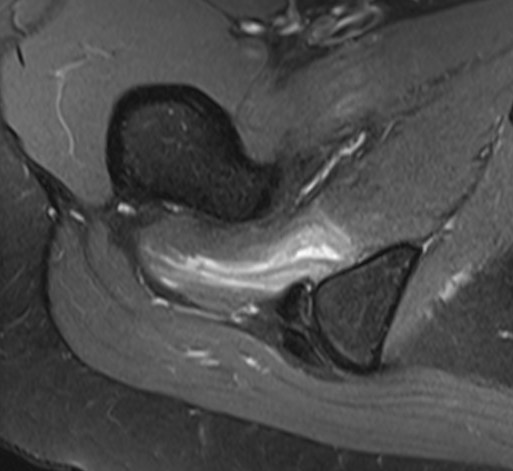

MRI

Reduced ischiofemoral space - distance between the lesser trochanter and the ischial tuberosity

Reduced quadratus femoris space - distance between hamstring tendon and iliopsoas

Inflammation / edema in quadratus femoris +/- fatty degeneration